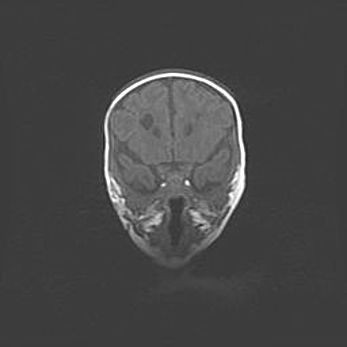

Лейкомаляция с кистозно-глиозной дегенерацией головного мозга.

Возраст: 2 месяца 25 дней

Вес: 6400 г

Окружность головы: 40 см

Срок гестации: 41 неделя

Лейкомаляцию относят к ишемически-гипоксическим повреждениям головного мозга, диагностируемым у новорожденных. При лейкомаляции в головном мозге обнаруживают очаги некроза, возникшие после тяжелой гипоксии и нарушения кровотока. В процессе морфогенеза очаги проходят три стадии: 1) развития некроза, 2) резорбции и 3) формирования глиозного рубца или кисты. Перивентрикулярная лейкомаляция (ПЛ) встречается примерно в 12% случаев среди новорожденных, обычно – у недоношенных детей, причем, частота ее зависит от массы, с которой младенец появился на свет. Наибольшее число малышей страдает лейкомаляцией, если масса при рождении 1500-2500 г.